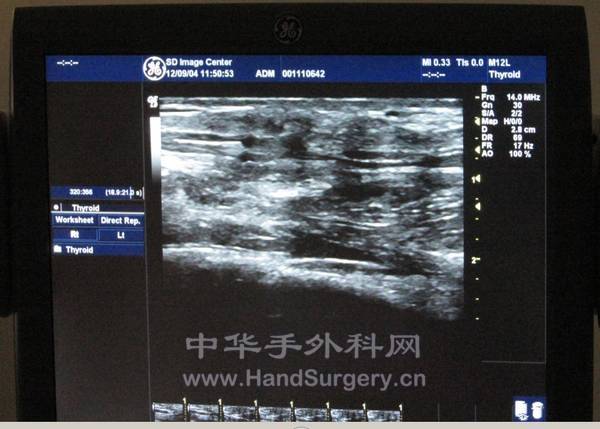

B超对上肢神经、肌腱损伤的诊断意义重大